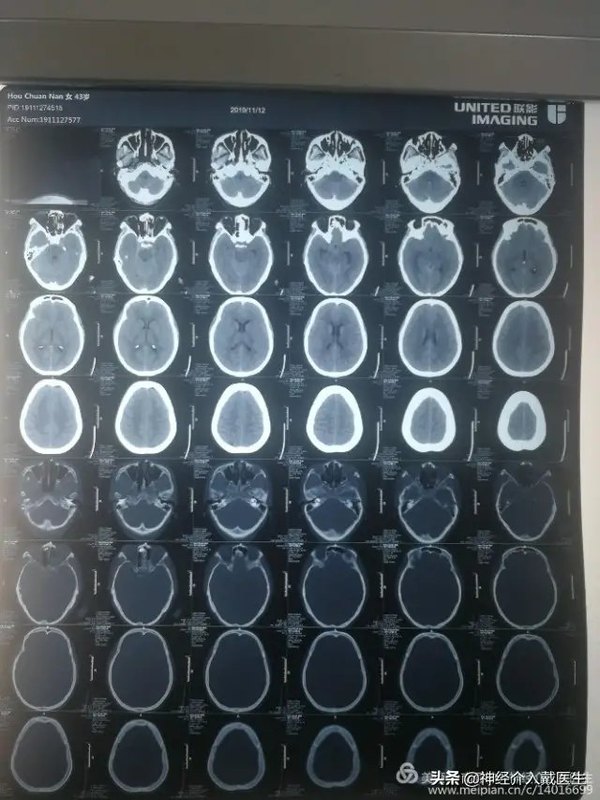

詩曰: 金蟾未動蟬先覺 , 暗算無常死不知 ; 溪云初起日沉閣, 山雨欲來風滿樓。 大病來襲前,多有一些蛛絲馬跡,智者識之,及時預(yù)防,可以防止出現(xiàn)災(zāi)難性后果,凡人則視而不見,危險將至。今天這個病人癥狀并不典型,開始的影像學檢查也不是很典型。 女,43歲,頭疼3天入院,加重并嘔吐一天于2019年11月12日收入南縣人民醫(yī)院神經(jīng)外科,病人既往高血壓病史5年,偶爾服藥治療,一般控制收縮壓145mmHg左右。 入院時候血壓167/102mmHg,神志模糊,GCS計13分,雙側(cè)瞳孔等大等圓,對光反射靈敏,頸抗,四肢肌力正常。 入院時候頭部CT:四腦室少量出血,如果不仔細看CT片子,可能還發(fā)現(xiàn)不了。是什么原因引起的四腦室出血?首先考慮血管性病變,首選還是腦血管造影。 腦血管造影顯示右側(cè)椎動脈V4段動脈瘤,并且是比較少見的夾層動脈瘤。長度大約9mm,動脈瘤破口與右側(cè)椎動脈重要分支右側(cè)小腦后下動脈很近。 動脈瘤最大的危險就是破裂出血,因為是大動脈破裂,壓力高,位于蛛網(wǎng)膜下腔出血,周圍腦組織相對不易壓迫止血,所以比一般的腦溢血更加危險,該部位動脈瘤出血直接壓迫生命中樞腦干,所以死亡率非常高,破裂后動脈瘤再出血幾率更加大,據(jù)統(tǒng)計動脈瘤再出血死亡率在70%左右。需要盡快手術(shù)治療。 動脈瘤手術(shù)經(jīng)典治療方式有開顱夾閉術(shù)和介入栓塞術(shù),該動脈瘤位于后循環(huán),后顱窩,腦干附近,顯露困難,并且是夾層動脈瘤,開顱夾閉術(shù)不合適,介入栓塞術(shù)是最好的選擇,該動脈瘤位于椎動脈重要分支右側(cè)小腦后下動脈開口處,所以保護右側(cè)小腦后下動脈是手術(shù)的重中之重。仔細觀看3D,動脈瘤破口與右側(cè)小腦后下動脈開口還是有一定的距離,又是破裂動脈瘤,支架加彈簧圈栓塞是最好的選擇,必要時可以用微導管或者支架保護右側(cè)小腦后下動脈。 確定了手術(shù)策略,具體就是注意一些細節(jié)了,做好術(shù)前準備,選擇好工作位。 通過真腔放置支架導管,放置彈簧圈導管,釋放一個5mm*12cm彈簧圈后,考慮需要保護小腦后下動脈,支架網(wǎng)孔大小很重要,我們選擇Enterprise2支架,4mm*23mm一枚, 依次釋放6mm*9cm,4mm*8cm,2mm*2cm,2mm*2cm彈簧圈各一枚,造影顯示動脈瘤腔致密栓塞。 復查椎動脈正位,動脈瘤不顯影,載瘤動脈及右側(cè)小腦后下動脈通暢。 復查椎動脈側(cè)位,動脈瘤不顯影,載瘤動脈及右側(cè)小腦后下動脈通暢。遂結(jié)束手術(shù)。 術(shù)后仍然劇烈頭疼,復查頭部CT排除顱內(nèi)遲發(fā)出血。 經(jīng)過一般藥物頭疼無明顯緩解,腰穿血性腦脊液,壓力390mmH2O,經(jīng)過多次腰穿放腦脊液后,頭疼逐漸緩解。 經(jīng)過十多天的積極治療,病人已經(jīng)恢復出院。 動脈瘤俗稱“顱內(nèi)定時炸彈”,一旦破裂30%多的病人未到醫(yī)院就已經(jīng)死亡,30%多的病人住院治療期間仍然死亡或者留下不同程度的后遺癥,只有1/3的病人經(jīng)過積極外科治療,能夠康復....... 對于破裂椎動脈動脈瘤,支架對于遠期血管重建和修復固然重要,而彈簧圈對于預(yù)防術(shù)后近期再出血更為關(guān)鍵! 把椎動脈動脈瘤分為兩型:Ⅰ型,不累及小腦后下動脈(PICA);Ⅱ型,累及PICA: 為什么以(小腦后下動脈)PICA是否受累分型?因為夾層是否累及PICA,決定了手術(shù)風險的評估和手術(shù)方案的制訂,甚至決定了遠期復發(fā)率。來自韓國人的一篇文獻認為,PICA受累是椎基底夾層動脈瘤介入治療后復發(fā)的獨立危險因素。 北京呂明把椎動脈動脈瘤的介入手術(shù)方案分為三種:A,載瘤椎動脈閉塞,即用彈簧圈閉塞夾層動脈瘤,并閉至近心端一段正常動脈;B,載瘤椎動脈重建,即用彈簧圈閉塞夾層腔,加以支架(單支架或多支架)重建載瘤椎動脈真腔;C,載瘤椎動脈閉塞加PICA重建,即用彈簧圈閉塞載瘤椎動脈,加以支架重建。 該病例采用B術(shù)式,目前取得滿意效果,但是仍然需要隨訪!